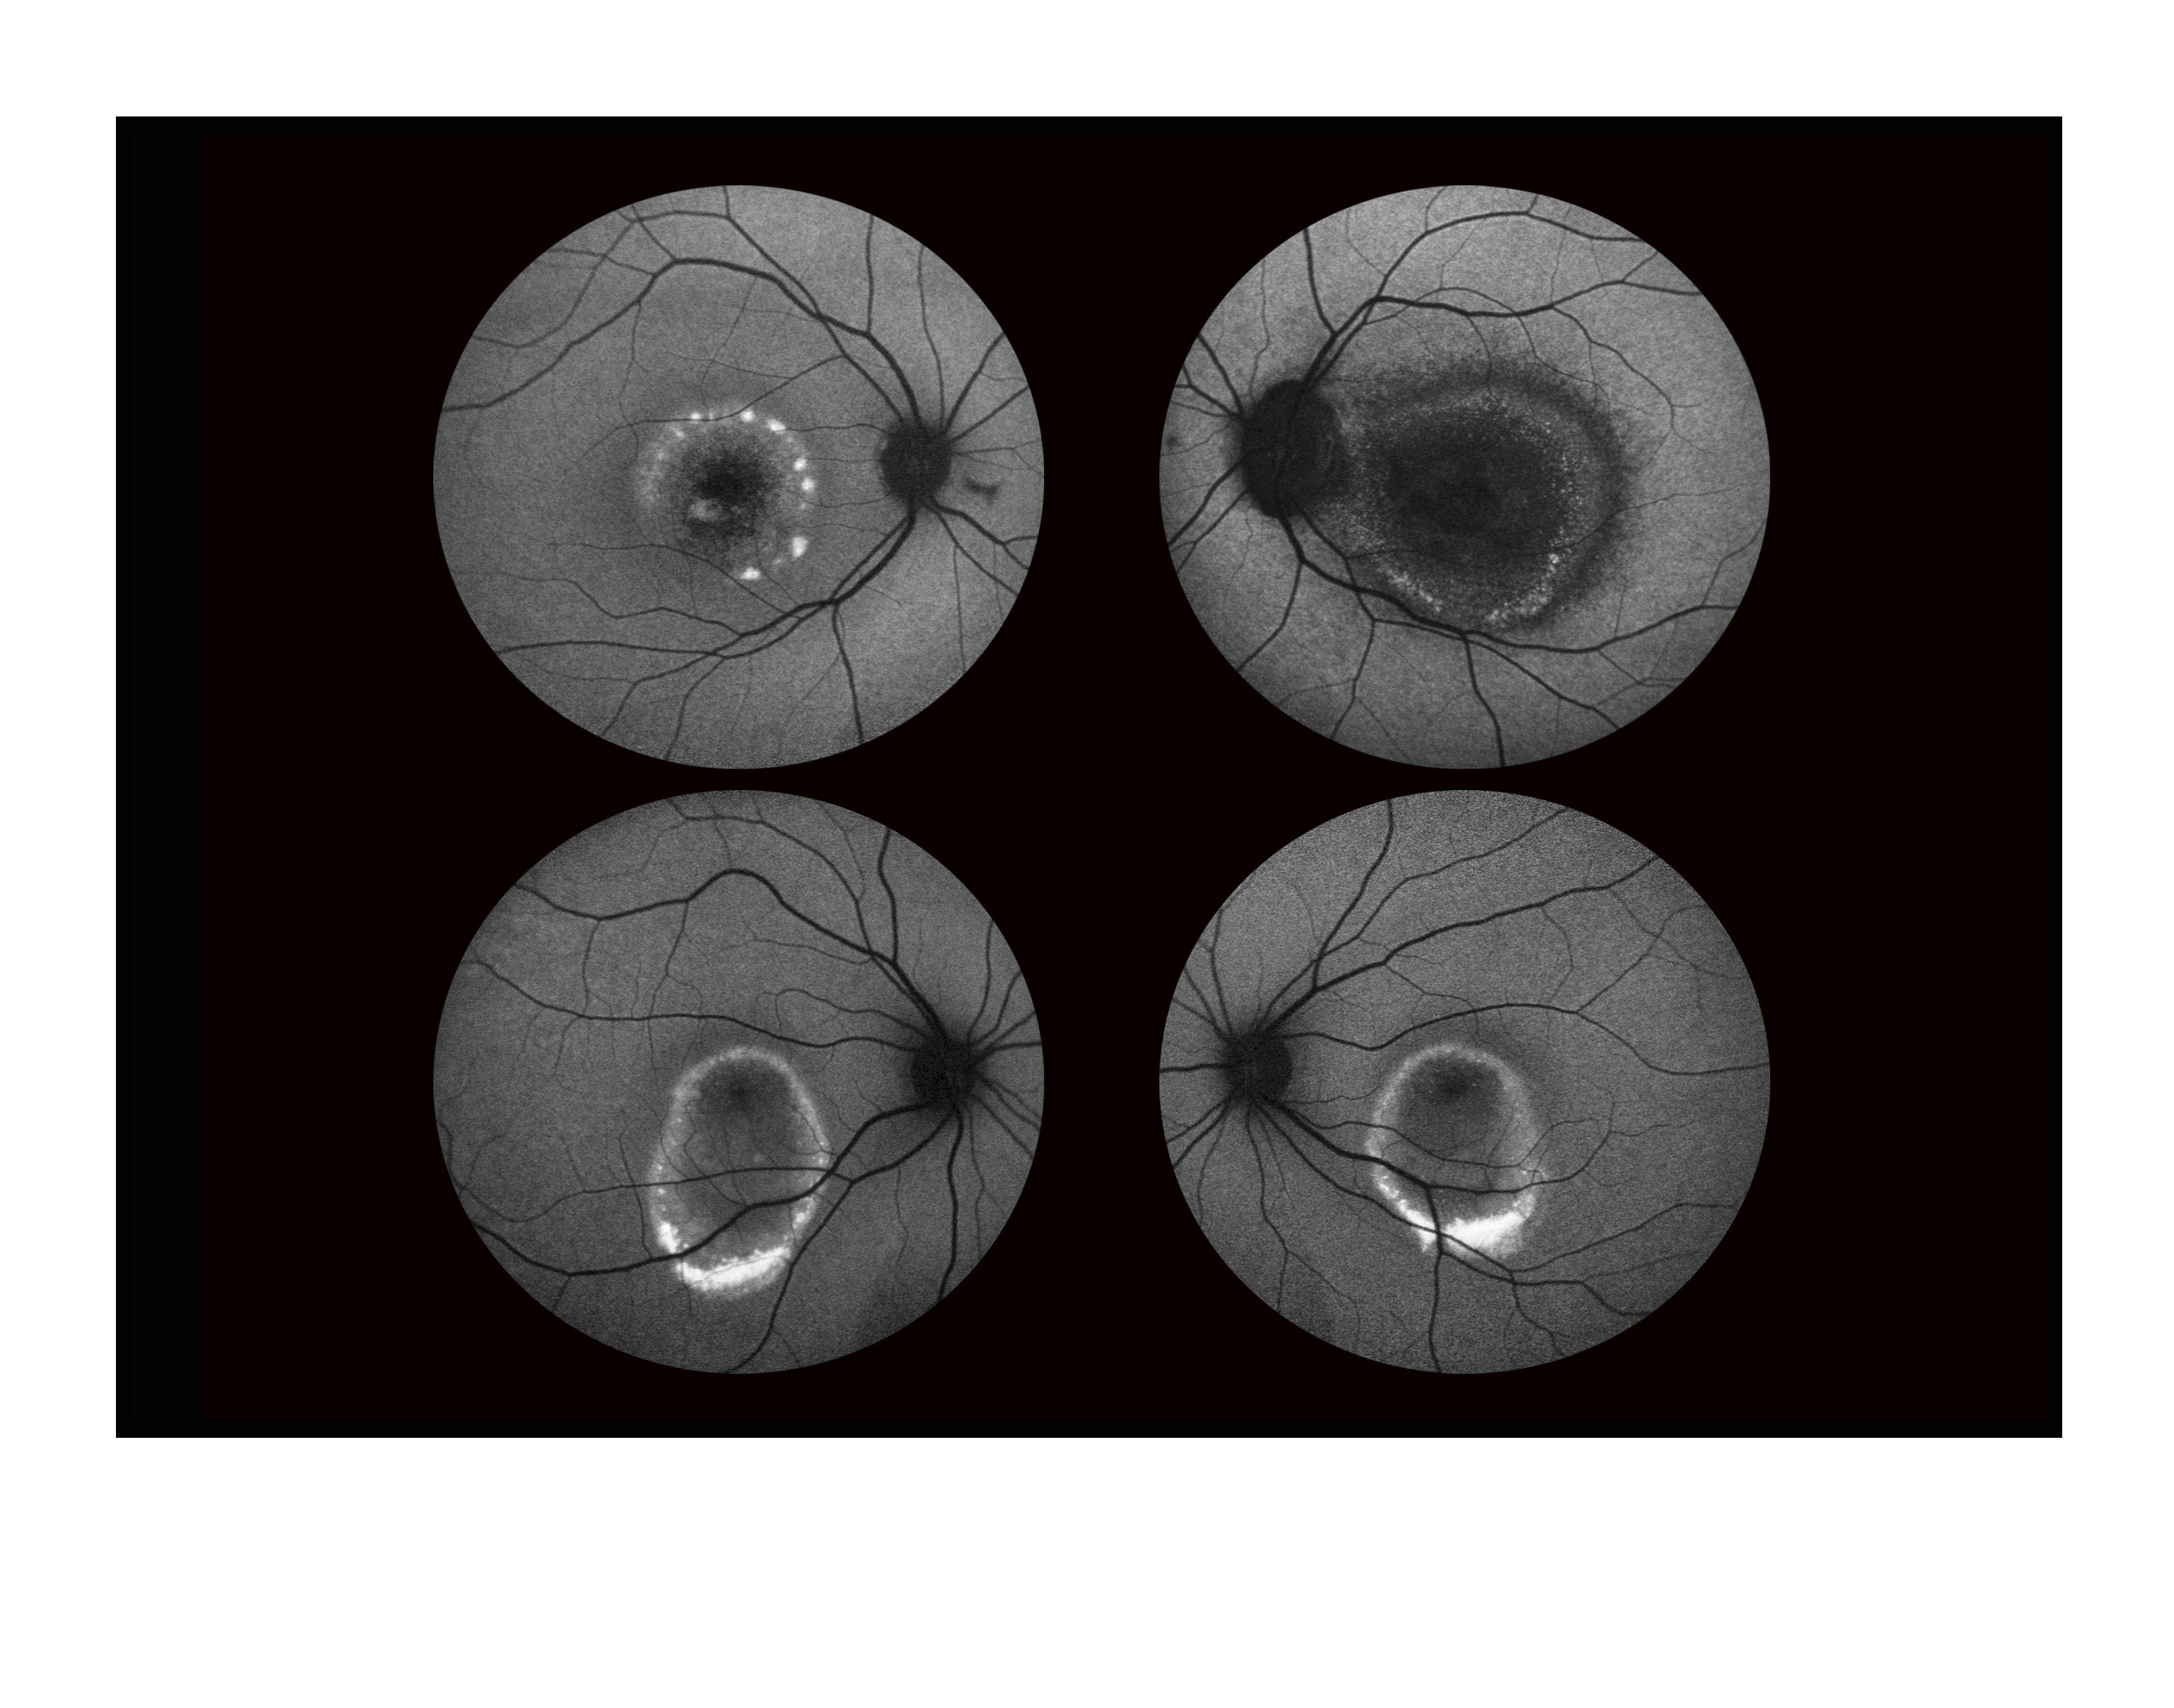

Father And Son With Best Dystrophy

Presented by Mark Harrod, CRA, OCT-C

This photograph received Second Place in the category "Fundus Autofluorescence" and was displayed in the 2024 OPS Exhibit.